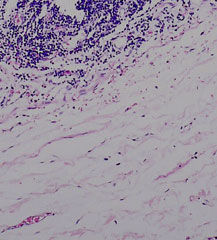

The mucosa is irregularly separating from the underlying submucosa due to post mortem autolysis.